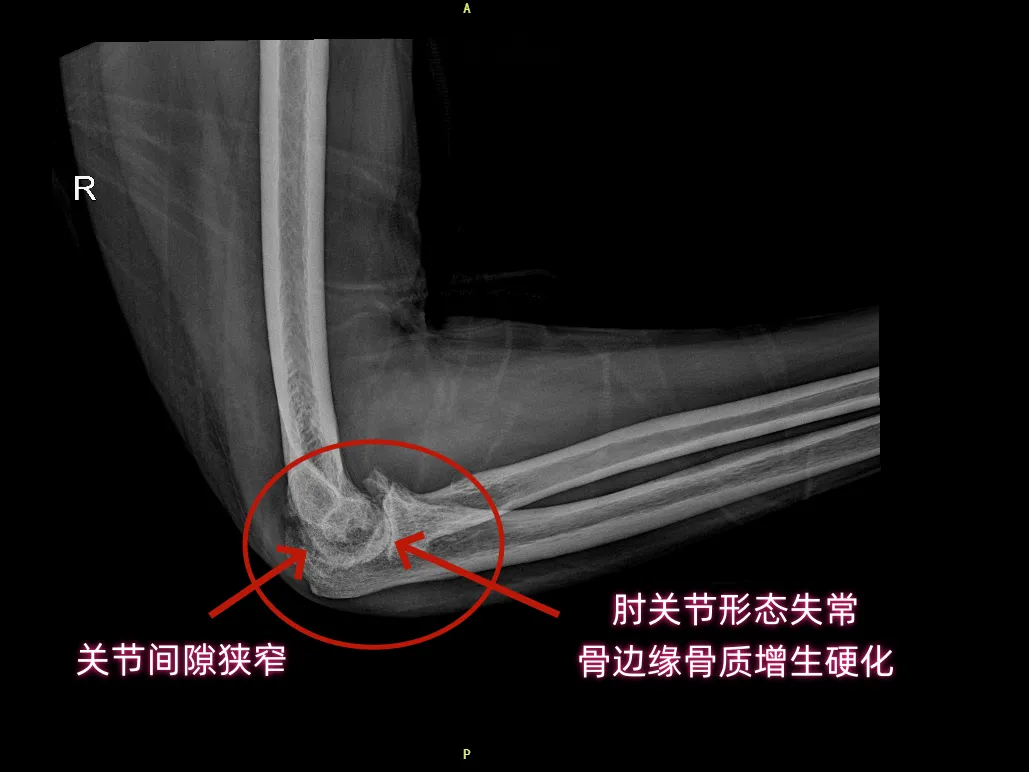

DR片显示:右肘关节诸骨边缘可见骨质增生、关节间隙变窄、关节面毛糙、密度增高——骨质已被长期炎症侵蚀。